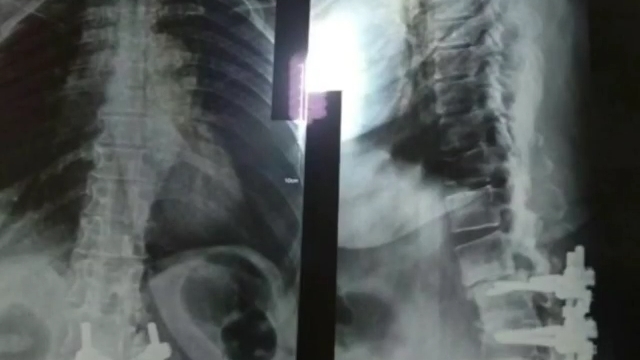

خانم ٦٠ساله ای که

چندین سال پیش مورد عمل کمری وسیله گذاری شده بود

و با شکستگی وسیله و اختلال بالانس شدید مراجعه کرده بود

و درد شدید کمری و اندام های تحتانی که بعد از عمل کاملا بهبود یافت.